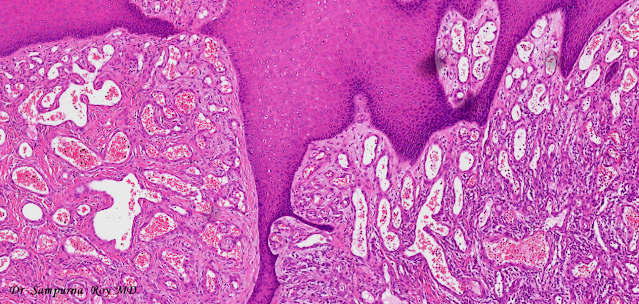

Dermatopathology Case 169 Get link Facebook X Pinterest Email Other Apps March 06, 2022 12 year-old boy with multiple warty congenital lesions over the dorsal aspect of the right foot. Answer Get link Facebook X Pinterest Email Other Apps Comments